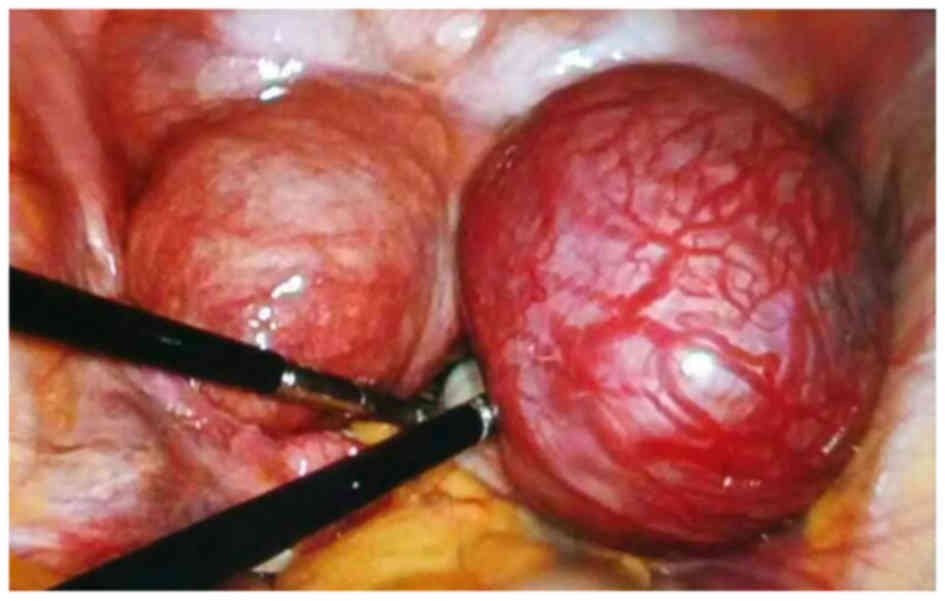

A combined hysteroscopy and laparoscopy was

performed 6 days subsequent to admission. The intraoperative

findings are shown in Fig. 3. The

uterus was increased in size, as is normal for a pregnancy at 2

months, and a normal ovary and fallopian tube was identified on the

left side. A rudimentary horn covered with tortuous and expansive

blood vessels, measuring 8×6×5 cm, was identified on the right side

of the uterus, with a normal ovary and fallopian tube attached. The

horn was connected to the right wall of the uterus above the

internal orifice of the uterus via a thin fibrous band. The

hysteroscopy revealed that the cervix and uterine cavity were

normal and that the left tubal opening was clear. However, the

right tubal opening could not be observed. The endometrium was

thick, presenting as an Arias-Stella reaction. As a result, the

rudimentary horn was dissected and diagnostic curettage was

performed by combined hysteroscopy and laparoscopy. The ipsilateral

adnexa was conserved as it appeared to be normal. The dissected

tissues were sent for routine pathological tests (Fig. 4).